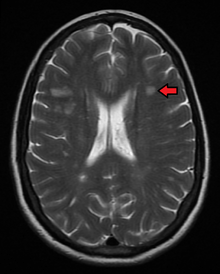

Clinical data alone may be sufficient for a diagnosis of MS if an individual has had separate episodes of neurological symptoms characteristic of the disease.[46] In those who seek medical attention after only one attack, other testing is needed for the diagnosis. The most commonly used diagnostic tools are neuroimaging, analysis of cerebrospinal fluid and evoked potentials. Magnetic resonance imaging of the brain and spine may show areas of demyelination (lesions or plaques). Gadolinium can be administered intravenously as a contrast agent to highlight active plaques and, by elimination, demonstrate the existence of historical lesions not associated with symptoms at the moment of the evaluation.[46][48] Testing of cerebrospinal fluid obtained from a lumbar puncture can provide evidence of chronic inflammation in the central nervous system. The cerebrospinal fluid is tested for oligoclonal bands of IgG on electrophoresis, which are inflammation markers found in 75–85% of people with MS.[46][49] The nervous system in MS may respond less actively to stimulation of the optic nerve and sensory nerves due to demyelination of such pathways. These brain responses can be examined using visual- and sensory-evoked potentials.[50]